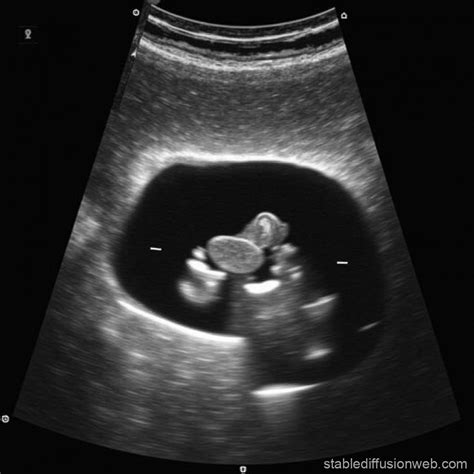

An ultrasound of the abdomen is commonly used during pregnancy to monitor the development of the fetus and detect any potential complications. Pregnant women may undergo multiple ultrasounds throughout their pregnancy to assess the baby's growth, check for congenital abnormalities, and determine the due date. Ultrasound is considered safe for both the mother and the developing fetus, as it does not involve radiation.

During pregnancy, the ultrasound technician will focus on the uterus and the developing fetus, evaluating various parameters such as:

• Fetal Heartbeat: Detecting and monitoring the baby's heartbeat.

• Fetal Size and Growth: Measuring the baby's size and assessing growth patterns.

• Placental Position: Evaluating the position and health of the placenta.

• Amniotic Fluid Levels: Checking the amount of amniotic fluid surrounding the baby.

• Fetal Anatomy: Assessing the baby's organs and structures for any abnormalities.

In some cases, additional ultrasound techniques such as Doppler ultrasound may be used to evaluate blood flow to the fetus and detect any potential issues with the placenta or umbilical cord.